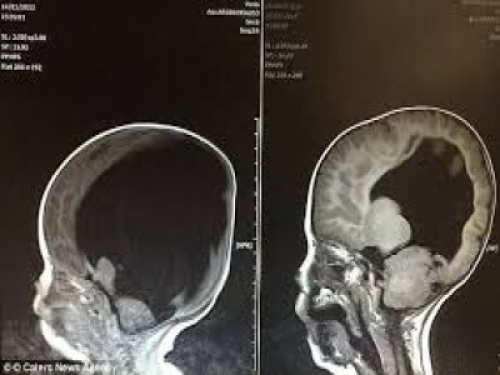

這個男孩是今年6歲的Noah Wall,他的父母Shelley和Rob日前帶著兒子一起接受電視訪問時表示,他們在懷孕的第3個月就發現Noah身上有許多問題。當時這對夫婦就被醫生勸了高達5次的墮胎建議,但他們不想要就這樣放棄他們的小孩,堅持把他生下來。所以當Noah出生時,許多醫生幫他檢查時發現他幾乎沒有大腦,只有不到 2%的「小腦袋」。然而,到了3歲時,腦部掃描顯示這個男孩的大腦已經長了塊80%!這到底是怎麽辦到的呢?